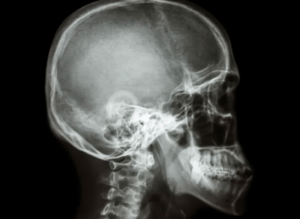

Telerradiografía lateral

Estas radiografías son una parte fundamental de los estudios de ortodoncia, ya que permiten medir los ángulos y proporciones de los huesos.